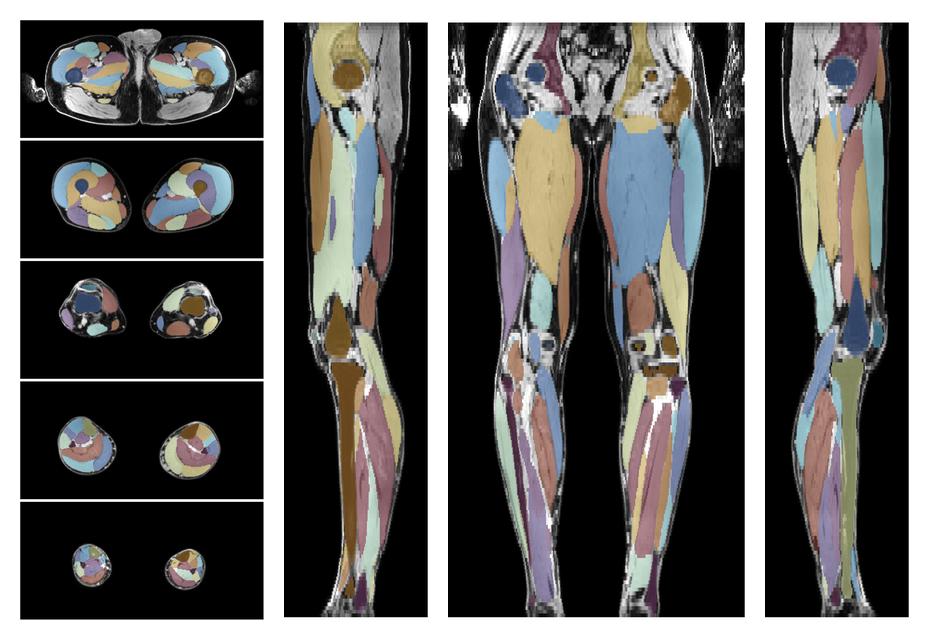

Muscle segmentation

Convolution neural network based (UNET) fiber automated muscle segmentation, for information look here».

• Automated muscle and bone segmentation.

Overlay of automated muscle segmentation labels on dixon water image.